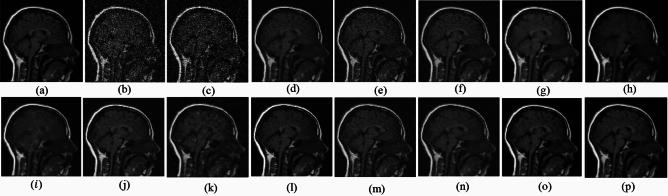

Medical imaging systems such as computed tomography (CT) and magnetic resonance imaging (MRI) are vital tools in clinical diagnosis and treatment planning. However, these modalities are inherently susceptible to Gaussian noise introduced during image acquisition, leading to degraded image quality and impaired visualization of critical anatomical structures. Effective denoising is therefore essential to enhance diagnostic accuracy while preserving fine details such as tissue textures and structural boundaries. This study proposes a robust and efficient denoising framework specifically designed for CT and MRI images corrupted by Gaussian noise. The method integrates a cluster-wise principal component analysis (PCA) thresholding approach guided by the Marchenko-Pastur (MP) law from random matrix theory and a non-local means algorithm. Noise level estimation is achieved globally by analysing the statistical distribution of eigenvalues from noisy image patch matrices and leveraging the MP law to accurately determine the Gaussian noise variance. An adaptive clustering technique is employed to group similar patches based on underlying features such as textures and edges and enables localized denoising operations tailored to heterogeneous image regions. Within each cluster denoising is performed in two stages where initially hard thresholding based on the MP law is applied to the singular values in the SVD domain to obtain a low-rank approximation that preserves essential image content while removing noise-dominated components. Residual noise in the low-rank matrix is then further suppressed through a coefficient-wise linear minimum mean square error LMMSE estimator in the PCA transform domain. Finally, a non-local means algorithm refines the denoised image by computing weighted averages of pixel intensities and prioritizing neighbourhood similarity over spatial proximity to effectively preserve edges and textures while reducing Gaussian noise. Experimental evaluations on CT and MRI datasets demonstrate that the proposed method achieves superior denoising performance while maintaining high structural similarity and perceptual quality compared to existing state-of-the-art approaches. The method demonstrates adaptability noise reduction capability and preservation of anatomical detail that make it well suited for precision critical medical imaging applications.

计算机断层扫描(CT)和磁共振成像(MRI)等医学成像系统是临床诊断和治疗规划中的重要工具。然而,这些模态在图像采集过程中固有地容易受到高斯噪声的影响,导致图像质量下降以及关键解剖结构的可视化受损。因此,有效的去噪对于提高诊断准确性同时保留诸如组织纹理和结构边界等精细细节至关重要。本研究提出了一种强大且高效的去噪框架,专门针对受高斯噪声破坏的CT和MRI图像设计。该方法集成了一种由随机矩阵理论中的马尔琴科 - 帕斯图尔(MP)定律引导的聚类主成分分析(PCA)阈值处理方法和一种非局部均值算法。通过分析噪声图像块矩阵的特征值统计分布并利用MP定律来准确确定高斯噪声方差,实现全局噪声水平估计。采用自适应聚类技术根据纹理和边缘等潜在特征对相似块进行分组,并针对异质图像区域进行局部去噪操作。在每个聚类中,去噪分两个阶段进行,首先在奇异值分解(SVD)域中基于MP定律应用硬阈值处理奇异值,以获得保留基本图像内容同时去除噪声主导成分的低秩近似。然后在PCA变换域中通过系数线性最小均方误差(LMMSE)估计器进一步抑制低秩矩阵中的残余噪声。最后,非局部均值算法通过计算像素强度的加权平均值并优先考虑邻域相似性而非空间邻近性来细化去噪图像,从而在减少高斯噪声的同时有效保留边缘和纹理。对CT和MRI数据集的实验评估表明,与现有的最先进方法相比,所提出的方法在保持高结构相似性和感知质量的同时实现了卓越的去噪性能。该方法展示了适应性降噪能力和解剖细节保留能力,使其非常适合精密关键的医学成像应用。